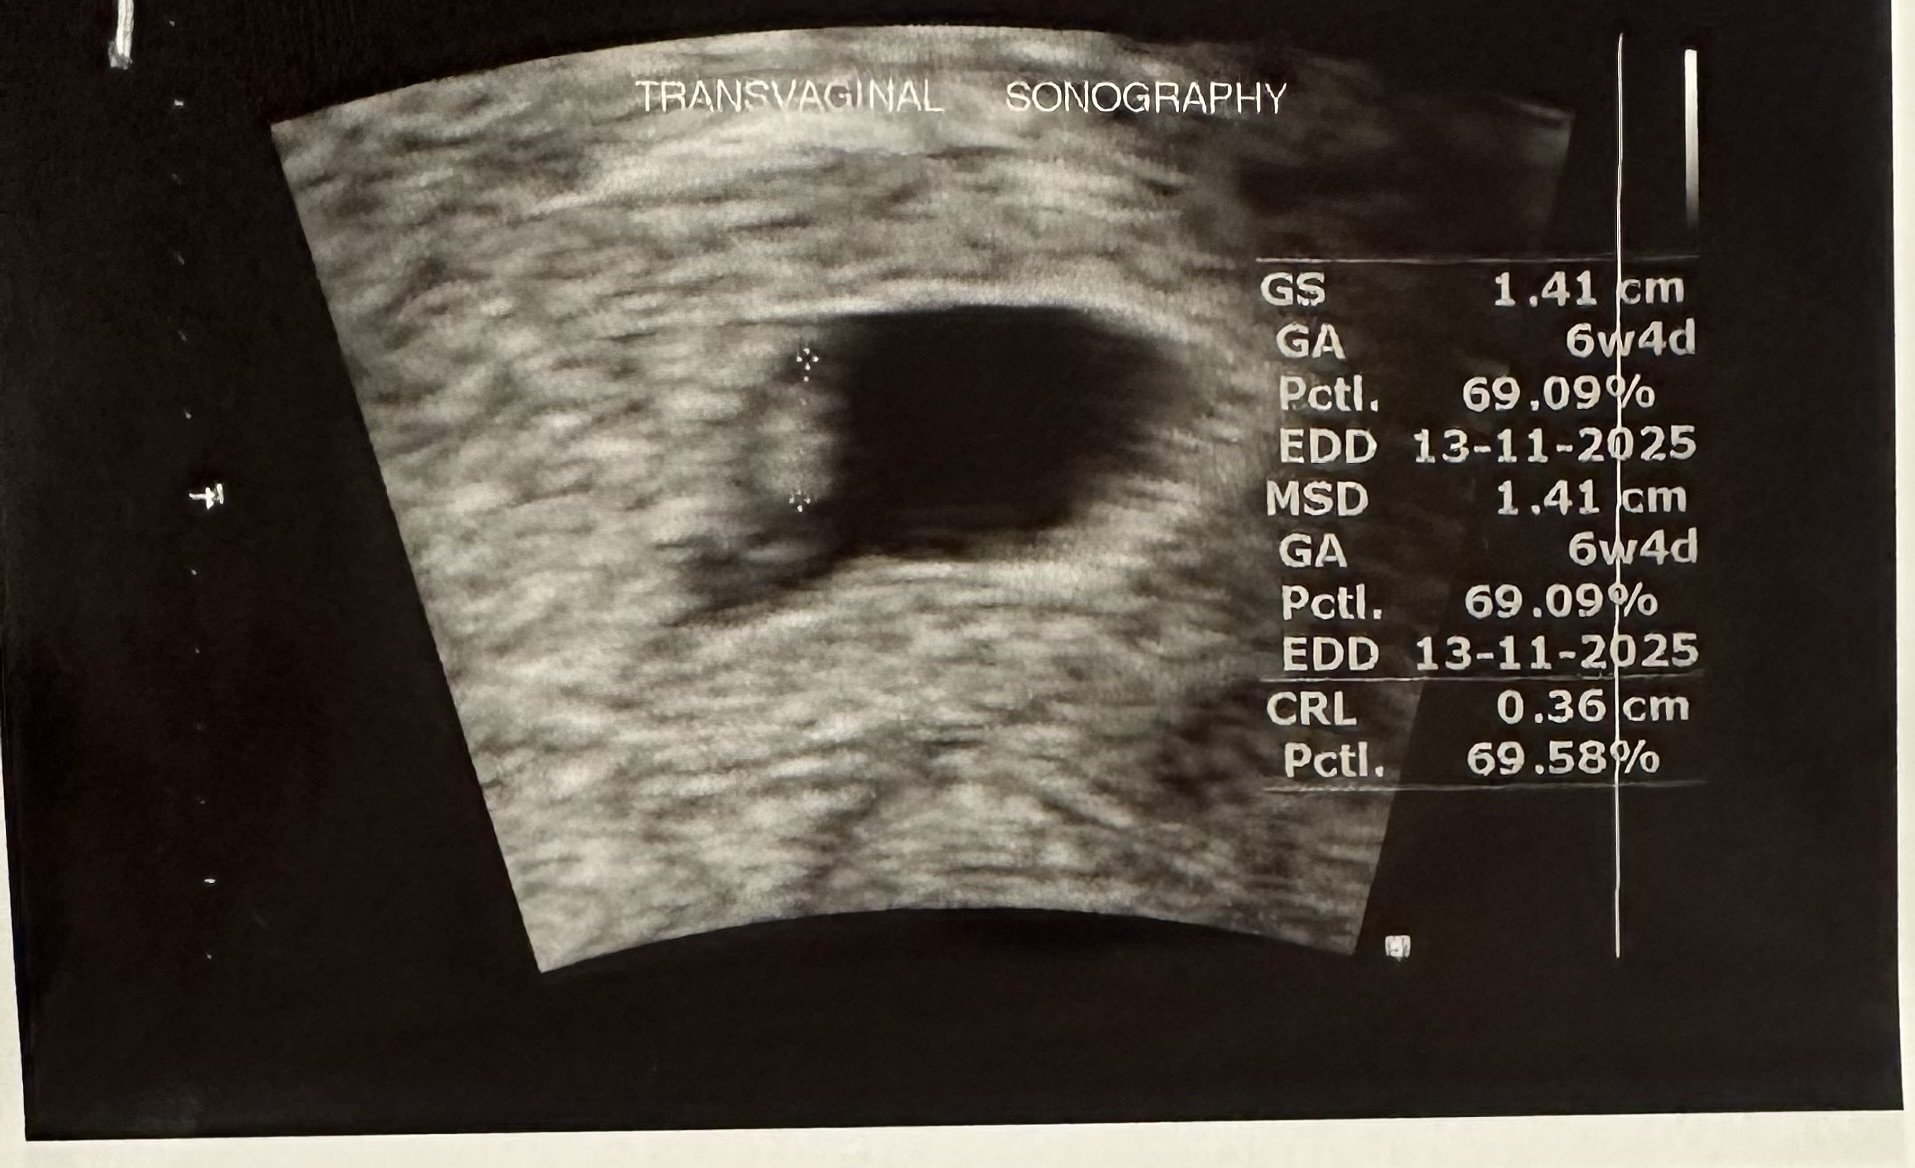

Според вас дали големината на ембриона , е добре за седмицата в която съм? Чухме и пулс. Доктора каза честито, но и накрая на прегледа каза на следващия преглед ще видим дали се развива, което малко ме притесни. Благодаря!

Здравейте! Може ли някой да ми каже дали всичко е наред? На първата снимка се видя, че бременността е маточна и каза, че всичко е наред, на втората снимка в 6 седмица все още не се чува пулс, каза, че плодния сак е пораснал и отговаря на седмиците си но каза нещо ембрионално не е пораснало. Не можах да разбера какво иска да каже с това, моля някой да ми помогне